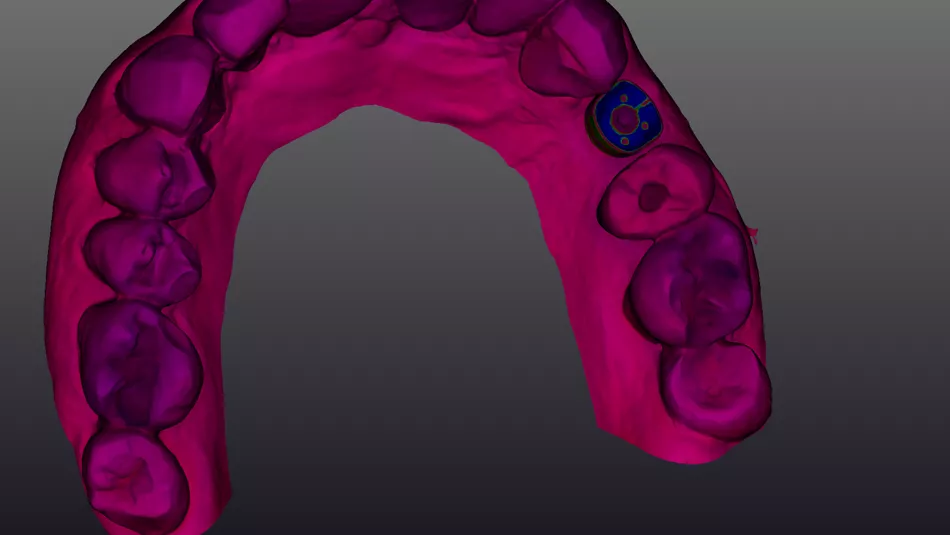

3a. 3b. Implant and Healfit® SH planning in coDiagnostiX®.Digital smile design illustrating esthetic outcome using Smilecloud®.

3a

3b

For the maxillary single‑tooth implant, a fully digital guided workflow was used, allowing a flapless approach. Soft‑tissue access was achieved with a tissue punch through the surgical guide [5], followed by osteotomy preparation using the Axiom® X3 drilling protocol. The implant achieved high primary stability (≈50 N·cm), enabling immediate placement of a HealFit® SH without suturing.

11a. 11b. 11c. 11d. Flapless guided placement of the maxillary implant with tissue‑punch access, Axiom X3 osteotomy, and immediate HealFit® SH placement without sutures.